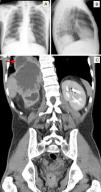

A 45-year-old man was admitted to the pulmonology department with a 2-week history of cough, sputum, hemoptysis and pleuritic chest pain on the right side. He reported anorexia, weight loss of about 6kg and excessive night sweating for the previous 2 months. For several months he had had recurrent episodes of dysuria, pollakiuria, nocturia and bilateral lumbar pain radiating to the groin. On physical examination, there were slightly decreased breath sounds in the right lung base and slight right flank pain on deep palpation. Chest X-ray (Fig. 1) revealed a rounded opacity in the right lung base, and thoracoabdominal computed tomography (CT) (Fig. 1) confirmed the presence of a large abdominal mass invading the thorax (see figure legend). Pathological examination of the lesion revealed poorly differentiated carcinoma of apparently urothelial origin. The patient started chemotherapy, but died about 8 months later due to disease progression.

(A and B) Chest X-ray (posteroanterior and lateral aspects, respectively) revealing a rounded opacity in the right lung base. (C) Thoracoabdominal CT (coronal plane) showing a large abdominal mass of about 13cm×11cm×8.3cm, apparently originating in the right kidney, invading the right lobe of the liver, the diaphragm and the lower lobe of the right lung (red arrow).